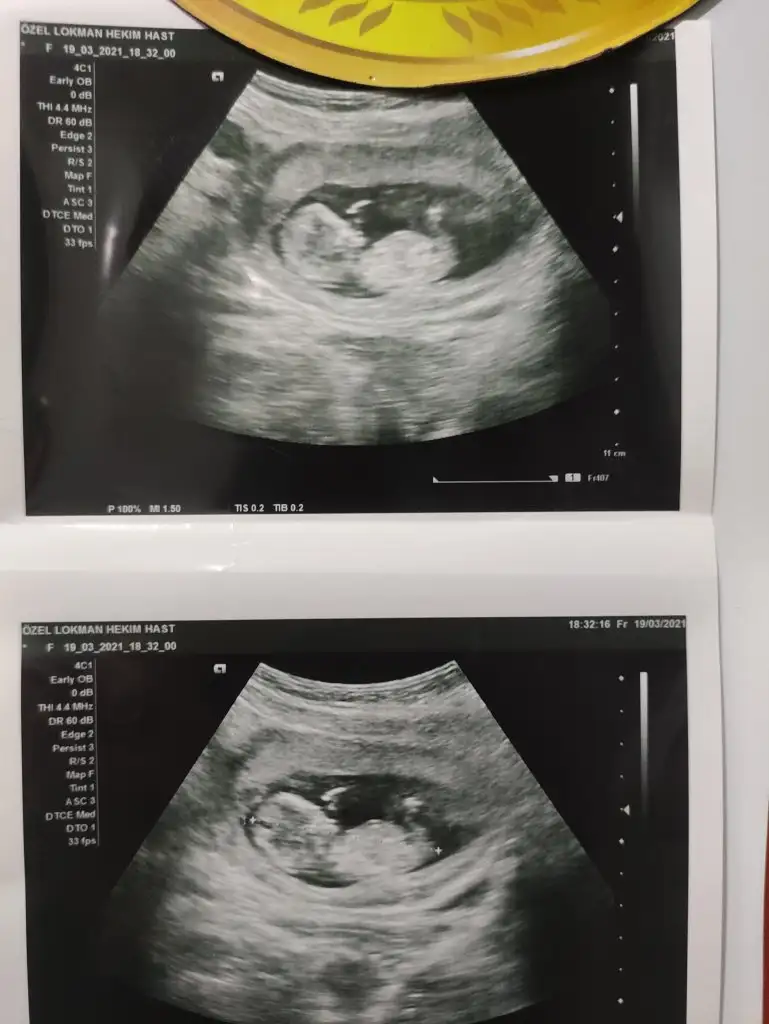

Kız görünüyor12+3üz, bize de bakar mısınız rica etsek?

Kız gibi sankiMerhaba ablamin bebegi bu yorumlarmisiniz benimkini bilmistiniz simdi sira bundaIkra meyra

Eki Görüntüle 2805103 Eki Görüntüle 2805104